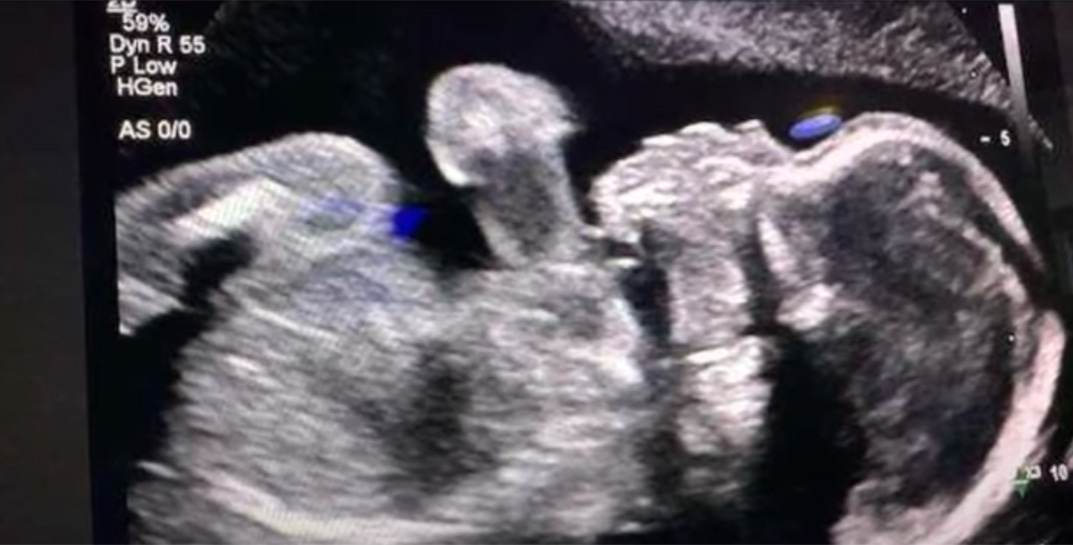

В Америке умершая женщина вынашивает ребенка, потому что в штате запрещены аборты

В Америке умершая женщина вынашивает ребенка, потому что в штате запрещены аборты Фото

21.05.2025, 12:38

В штате Джорджия больница три месяца держит на аппаратах жизнеобеспечения беременную женщину, которой констатировали смерть мозга. Все из-за закона, запрещающего аборты.